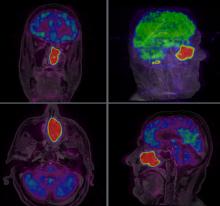

Two new studies show that increasing the dose of radiotherapy given to children with an intracranial ependymoma, a form of cancer of the central nervous system, can significantly improve their survival. Results of both studies were presented at the third European Society for Radiotherapy and Oncology (ESTRO) Forum in Barcelona, Spain.